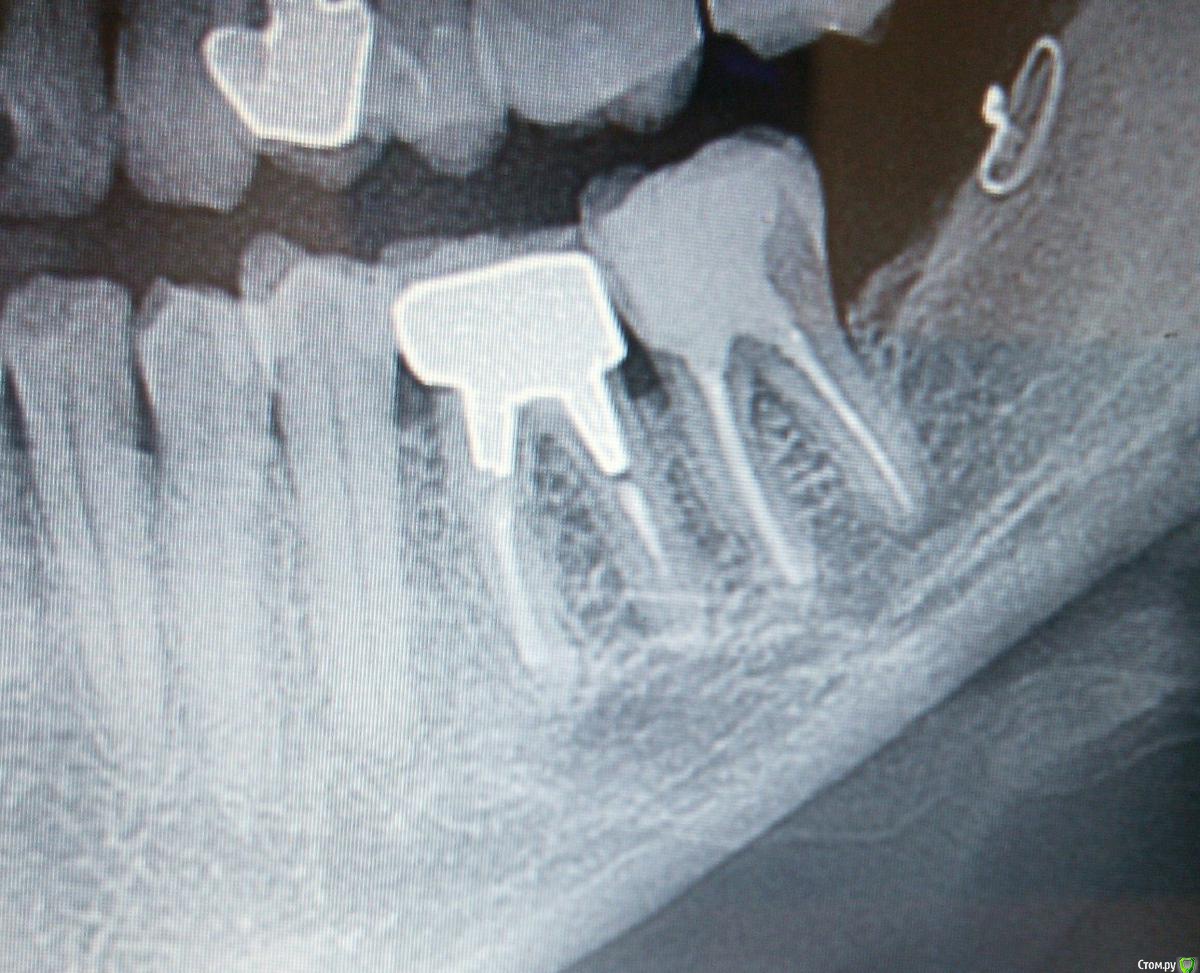

igorstom Опубликовано 24 ноября, 2019 Автор Поделиться Опубликовано 24 ноября, 2019 Вот пример работы через некоторое время с гемисекцией. Можно конечно задать резонный вопрос: почему каналы не пролечены.... Объясняю. Работа делалась абсолютно бесплатно. Ну человек такой мне попался - блатной, родственница начальников. А как известно бесплатный сыр только на сыр-заводе. Поэтому с каналами в данном случае просто не стал заморачиваться. Ведь по "леченым" каналам видно, что пациентка лечилась всегда на халяву с вытекающими отсюда последствиями для своих зубов. А перелечка чужого эндо это всегда сильный геморрой. Работа проводилась в Госке. 2 Ссылка на комментарий